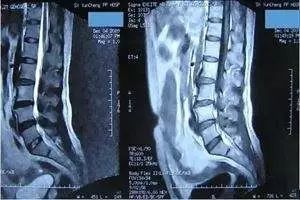

六、如何看腰椎CT/MRI片子矢状面图 图(七)的CT片是来自左侧图层的下面,将椎间盘的后部表现得相当地好。

下面小编就介绍下这个正常的腰椎在CT下的解剖结构。平行于椎体终板作腰椎横断CT扫描,正常腰椎

正常椎间盘ct图片 17-12-25 韩庄正骨+关注 献花(0)收藏 学会看腰椎间盘突出ct和mri磁共振片子的超好教程1